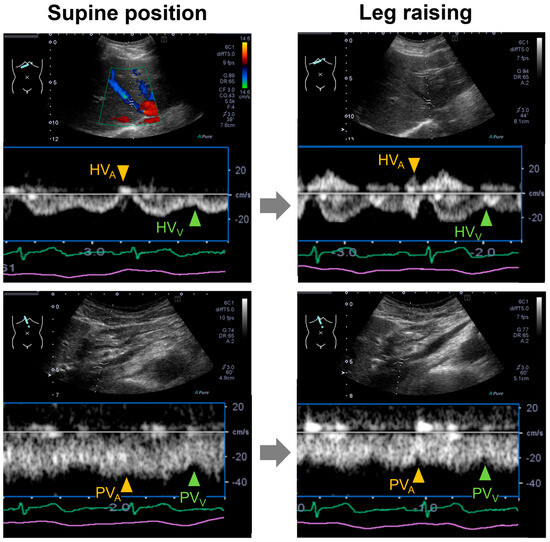

Portal venous (PV) flow Doppler velocimetry assesses venous congestion in heart failure, showing PV pulsatility due to backward transmission of right atrial pressure (RAP) through the sinusoids. However, PV pulsatility has also been observed under physiological conditions. We aimed to elucidate the mechanisms and contributing factors of PV pulsatility in healthy adults. Pulsed-wave Doppler recordings of the hepatic venous (HV) and PV flow were obtained with electrocardiography. A- and V-wave velocities and their timings relative to the P- and R-waves (P-HVA, R-HVV) were measured from the HV waveforms. From PV waveforms, atrial and ventricular systolic descent flow velocities and their timings (P-PVA, R-PVV) were measured. The PV pulsatility index (VPI) was calculated. There were no differences between P-PVA and P-HVA, and between R-PVV and R-HVV, indicating similar waveforms. Seventy-nine percent of participants showed a VPI ≥ 0.3, with a higher VPI in younger vs. older participants (0.7 vs. 0.3, p < 0.01). Only age was independently associated with VPI (β = −0.56, p < 0.01). PV pulsatility was common in healthy adults, suggesting RAP transmission via the sinusoids; this physiological phenomenon was attenuated with aging. These findings highlight the importance of considering age-related physiological changes when interpreting the PV flow. Full article